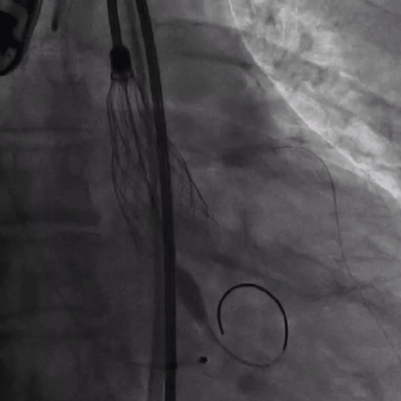

导丝左冠保护

导丝跨瓣

18mm球囊预扩,无明显腰征,少许瓣周漏,未见冠脉阻挡,决定选择TaurusOne®AV23瓣膜。

瓣膜定位

瓣膜释放后形态位置良好,造影无返流